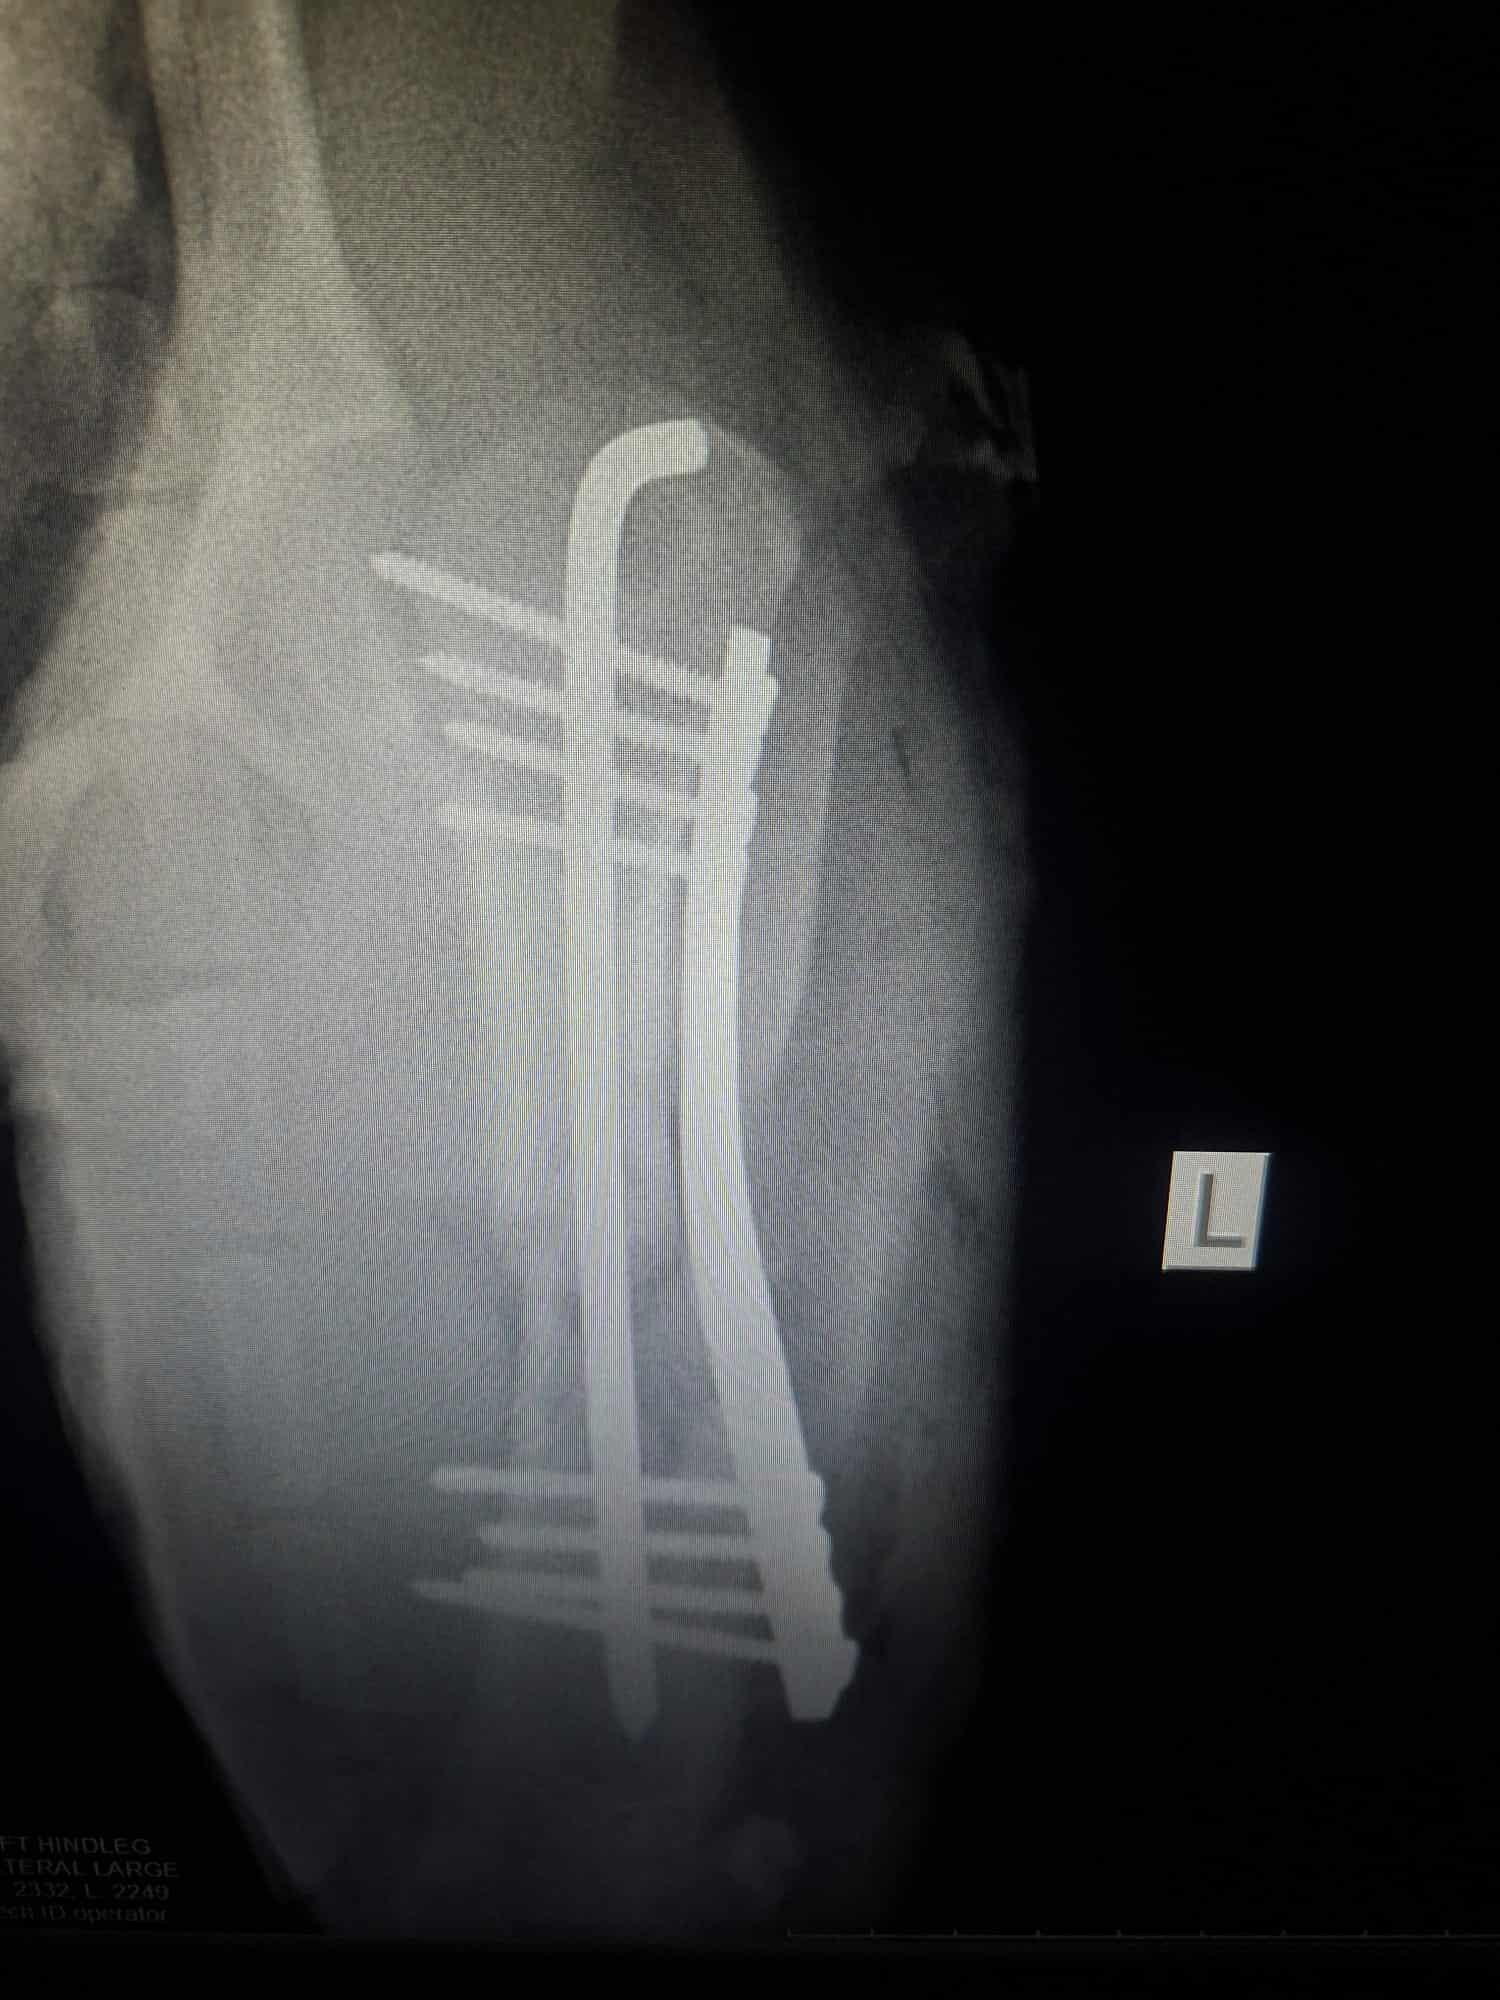

Conduit d’urgence chez le vétérinaire, le diagnostic est tombé : Lupi souffre d’une fracture du fémur et d’une fracture de la tête qui nécessite une prise en charge immédiate.